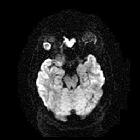

MRI

Signal characteristics include:

- T1: intermediate intensity lacrimal fossa mass

- T2: usually hyperintense

- T1 C+: heterogeneous enhancement

- DWI and ADC: diffusion restriction of the peripherally enhancing component